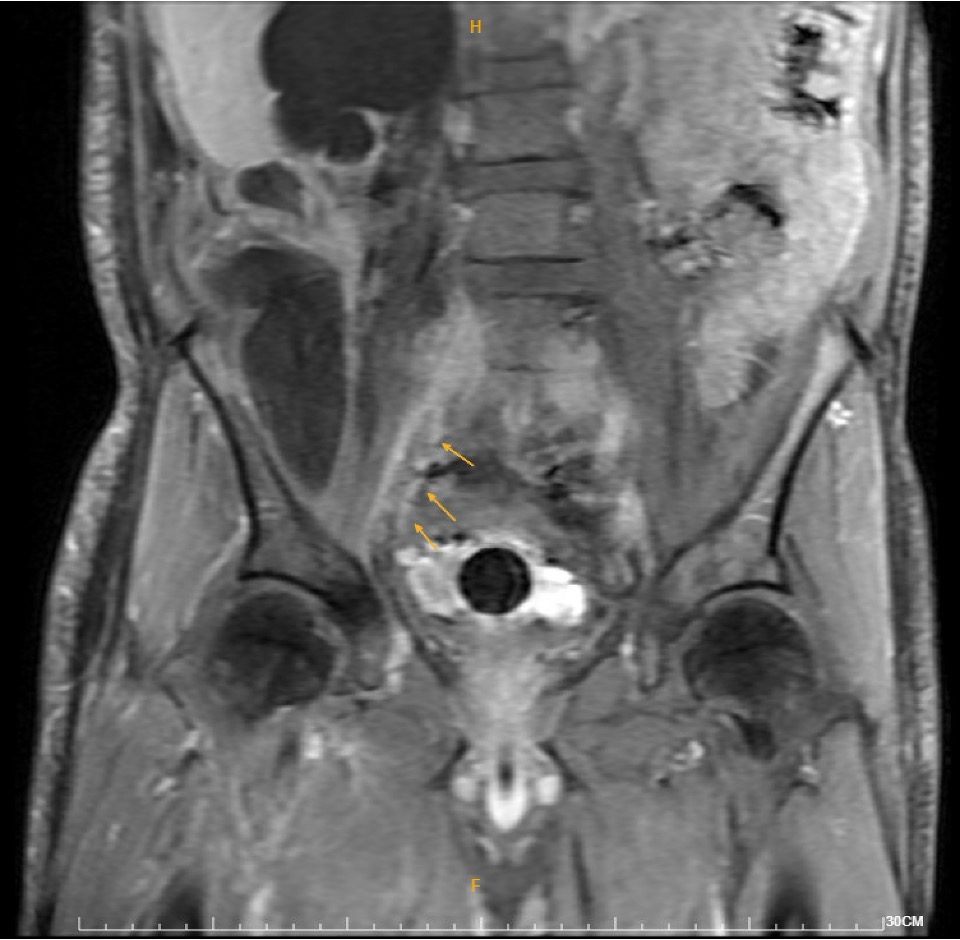

Duplex ultrasound demonstrated thrombosis from the right common femoral vein to the calf veins. MRI revealed a 16.8-cm retroperitoneal fat-containing tumor causing severe right hydronephrosis, and extensive thrombosis involving the right common, external, and internal iliac arteries, lower IVC, iliac, and femoral veins. DVT intervention was arranged.

Catheterization revealed total occlusion of the right common iliac artery, likely due to tumor compression. Diffuse thrombosis was seen in the right common femoral vein, with total occlusion from the right common iliac vein to proximal RCFV. LCIV ostial stenosis (~80%) and IVC stenosis (~90%) were also present.